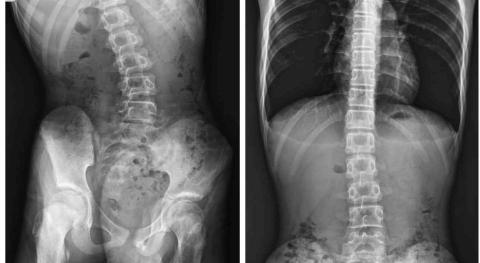

態優健護賦能中心桃園中山店 - 脊椎側彎

態優健護賦能中心桃園中山店 - 客戶脊椎側彎回傳前後圖